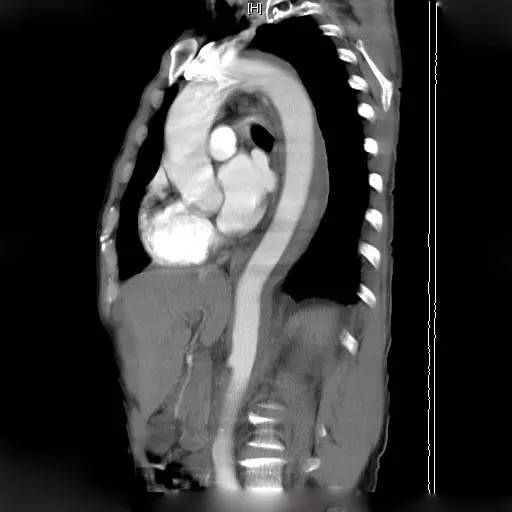

2.1 CT表现通常是主动脉壁呈新月或环形增厚,而主动脉真腔可发生变形或略变细,如图1所示,也可以正常。增强CT对IMH的显示通常优于平扫CT。